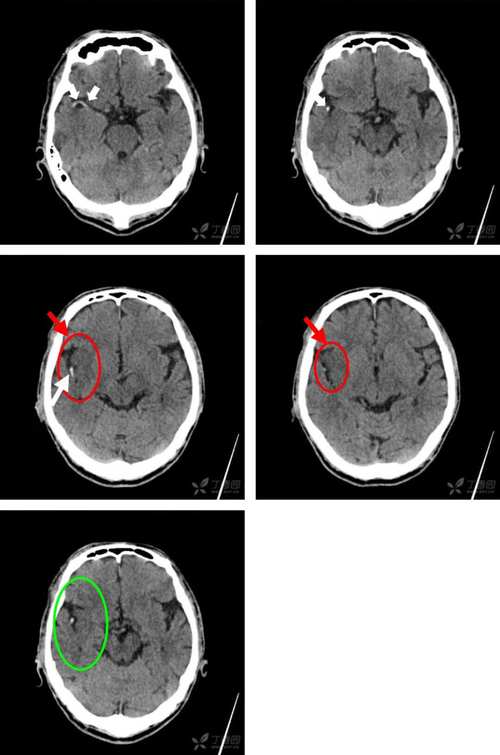

- 影像表现:在DWI图像上,新梗死的区域会显示为明显的高信号(亮白色),在另一个叫做“表观弥散系数”(ADC)的序列上,同一个区域会显示为低信号(暗黑色),这种“DWI高信号,ADC低信号”的组合是诊断急性期(通常指6小时内到2周内)脑梗死的“金标准”。

- 影像表现:在DWI和ADC序列上,陈旧梗死的区域通常没有上述的信号异常,它可能表现为一个与脑脊液信号相似的、边界清晰的低信号区(在T2序列和FLAIR序列上更明显),周围可能有胶质增生形成的信号改变。

- 明确责任病灶:医生会结合您的临床症状(如偏瘫、失语、口角歪斜等),确定MRI上显示的新发梗死区域是否是导致您当前症状的原因。

- 评估梗死类型和机制:

- 大血管闭塞?:医生可能会安排磁共振血管成像(MRA)或CT血管造影(CTA),查看颅内大血管是否有堵塞或严重狭窄,这是决定是否进行静脉溶栓或机械取栓的关键。

- 小血管病变?:如果梗死灶很小,位于脑深部,可能提示小血管病变(如高血压引起的腔隙性脑梗)。